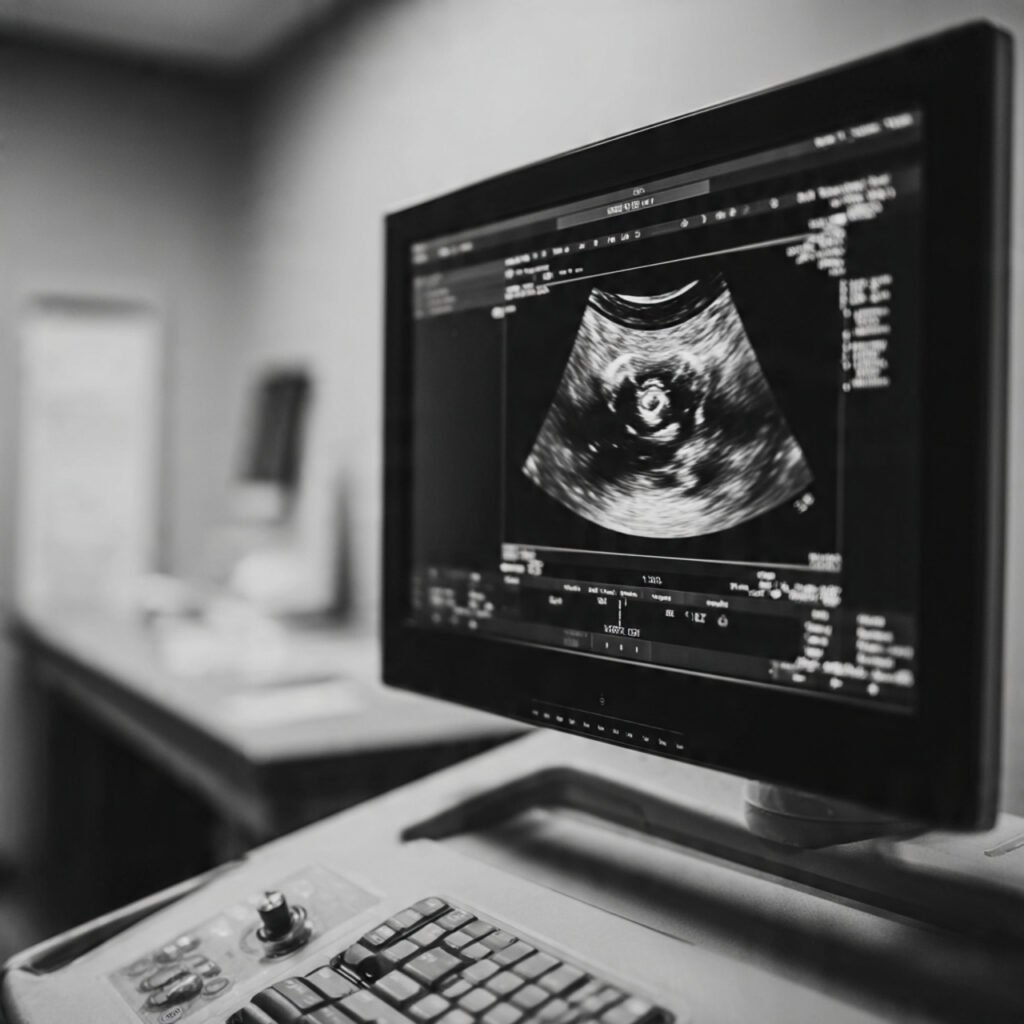

Founder of Nisarga Diagnostics, is a renowned fetal ultrasound specialist with over 20 years of expertise. An alumnus of Government Medical Colleges in Mysore and Bangalore, he also holds a D.N.B. from the National Board of Examinations, Delhi, and certification from the Fetal Medicine Foundation, London. A former Professor and HOD, he has trained countless PG students and junior radiologists, shaping the future of fetal imaging in India.